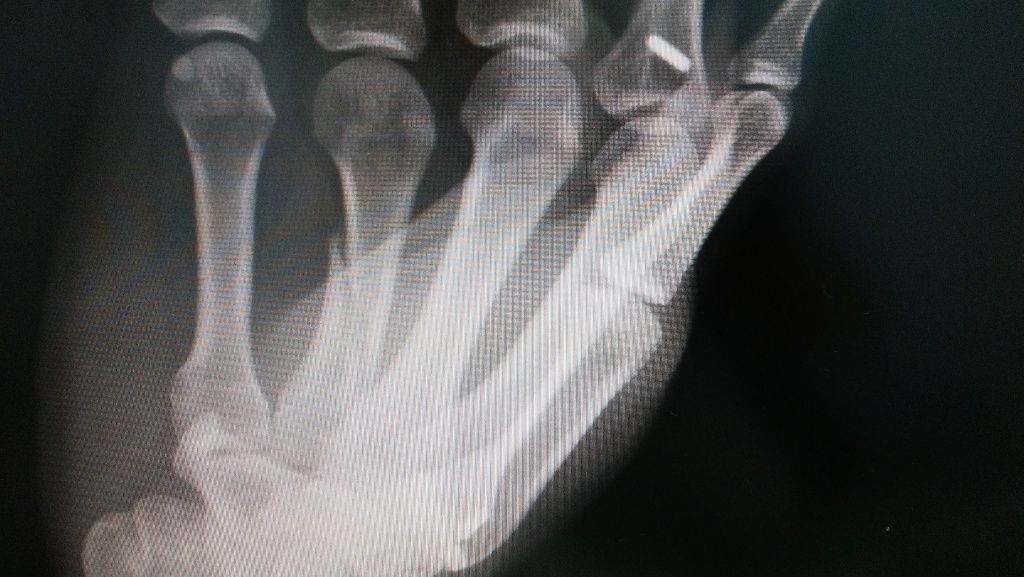

転位骨折 4週で 癒合

イメージ 2